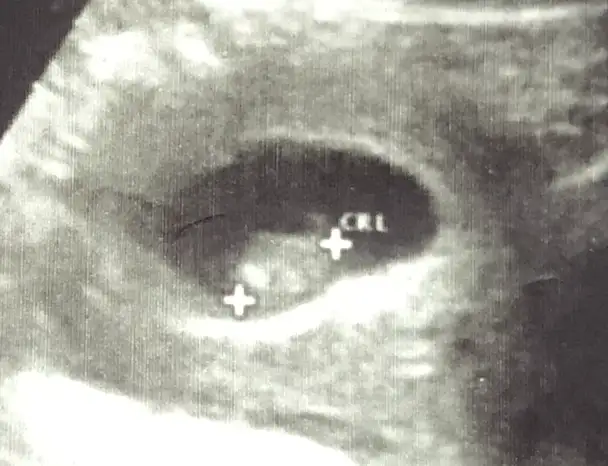

6-7 haftalık ultrason varmı yollar mısın Bi daha bakim merak ettimNisan sonu- Mayıs başıartık 18 oluyor öğreniriz heralde

ben de araya kaynasam? daha önce buraya atmıştım ama hiç tahminde bulunan olmadı.ilki 6 hafta ikincisi 7+3.6-7 haftalık ultrason varmı yollar mısın Bi daha bakim merak ettim

doktor bir şey demedi ama.Vajinal ultrason ise erkek karın ultrasonu ise kızben de araya kaynasam? daha önce buraya atmıştım ama hiç tahminde bulunan olmadı.ilki 6 hafta ikincisi 7+3.

Kız bence

Kıza benziyor

Bana da yorum yapar mısınKıza benziyor